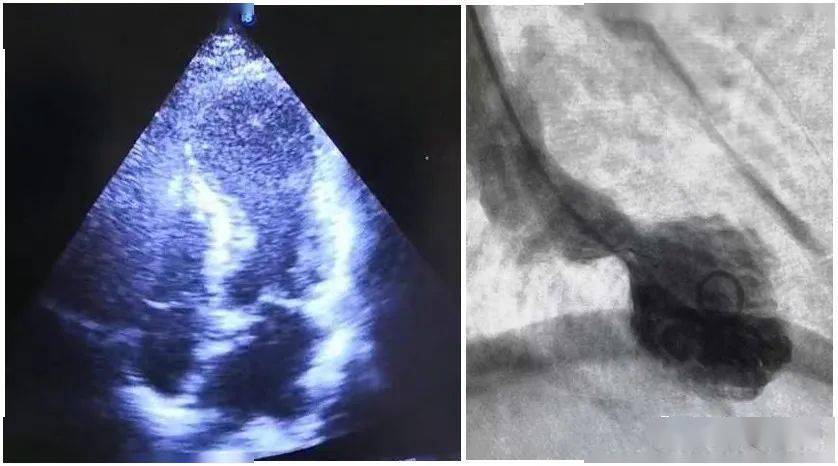

医生当即决定做左室造影 , 果然见到左心室收缩期时心尖部呈现球样化改变 , 而随后心脏超声下 , 也见到了“章鱼篓”样心脏形态 , 证实了这个诊断 。

曾女士的左心室造影图

如果将大多数应激性心肌病患者的心脏放在超声下看 , 会发现患者的心尖部分像个球形 , 所以这种病也可以叫做“心尖球化综合征” , 因为此时心尖的形状像 日本渔民捕鱼用的章鱼篓 , 所以也有人称之为“章鱼篓心肌病”( 这是因为此时左室心尖和前壁下段运动减弱或消失 , 基底部心肌运动则代偿性增强 , 因而在收缩末期呈底部圆隆、颈部狭小导致的) 。